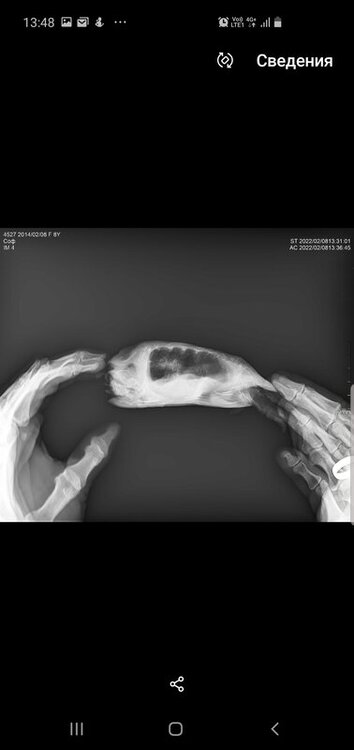

Консультанты moth Ваше имя: Мария Локация: Москва Опубликовано: 8 февраля 2022 Консультанты Опубликовано: 8 февраля 2022 @Зюлиф нет, к сожалению я в снимках могу только что-то простое увидеть - газы или яйца или инородное тело. У Вас всё сложно из-за деформации панциря.

Зюлиф Ваше имя: Софа Локация: Набережные Челны Опубликовано: 8 февраля 2022 Автор Опубликовано: 8 февраля 2022 1 час назад, moth сказал: @Зюлиф нет, к сожалению я в снимках могу только что-то простое увидеть - газы или яйца или инородное тело. У Вас всё сложно из-за деформации панциря. Все же прикреплю пару фото.И вопрос:сегодня доставили уф лампу simple zoi bulk UVB10.0 13W,на каком расстоянии вешать ее от островка,подскажите, пожалуйста

Консультанты moth Ваше имя: Мария Локация: Москва Опубликовано: 8 февраля 2022 Консультанты Опубликовано: 8 февраля 2022 @Зюлиф я тут вижу только, что лёгкие мутные, но это могут и органы перекрывать. Я понимаю, что ожидание ответа может быть некомфортным, но это в реальности быстрее очных приёмов тех же самых, на них может быть запись и неделю-две.

Консультанты moth Ваше имя: Мария Локация: Москва Опубликовано: 10 февраля 2022 Консультанты Опубликовано: 10 февраля 2022 @Зюлиф как нету, в 2.35 она Вам написала, посмотрите телеграмм По поводу рентгена: - Объем легких незначительно снижен - Есть признаки скопления экссудата (жидкости), что может говорить как раз о пневмонии. - Плотность костных структур снижена, неравномерная. а дальше как раз про лечение и антибиотик